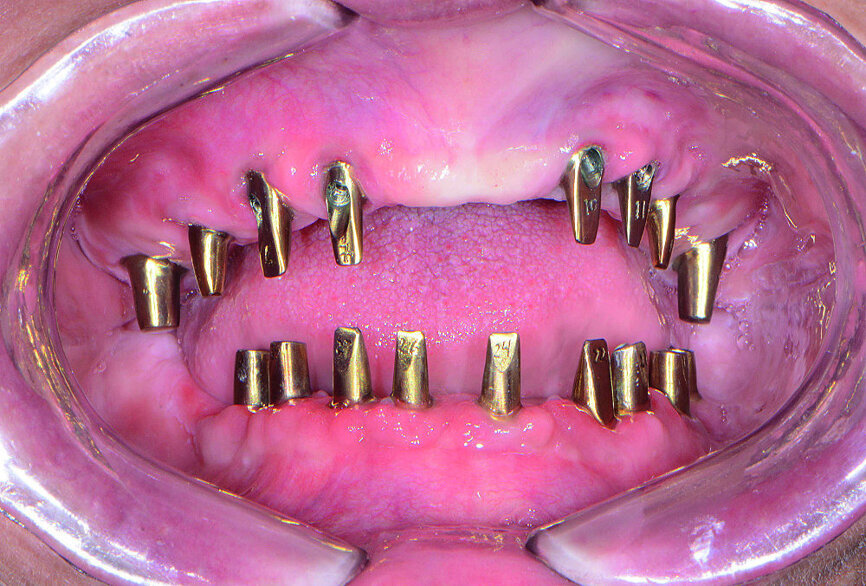

La patiente est revenue pour une évaluation clinique du modèle prothétique. Les piliers personnalisés ont été mis en place à l’aide de guides de positionnement en acrylique, fournis par le laboratoire pour faciliter l’orientation adéquate pendant l’insertion (Fig. 19). Grâce à la précision de la technique de conception numérique, l’ajustage des piliers personnalisés s’est révélé parfait et définissait des limites marginales positionnées exactement, ou à une distance négligeable de la surface gingivale. Cette précision a fortement simplifié l’élimination de l’excès de ciment des limites marginales et illustre les avantages des piliers produits en CFAO.

Les composants du sourire en PMMA ont été ajustés sur les piliers personnalisés et de légères modifications ont été apportées pour parfaire le rebord marginal de la gencive, la longueur des dents et l’occlusion (Fig. 20). Un enregistrement occlusal a été réalisé au moyen des bridges conçus pour l’essayage. Les composants du sourire en PMMA ont été retournés au laboratoire en même temps que les photographies, l’enregistrement occlusal et des instructions concernant des modifications mineures, notamment une réduction de la limite marginale gingivale de la prothèse mandibulaire et un rehaussement de la limite marginale gingivale de la prothèse maxillaire. Le laboratoire a scanné les bridges en PMMA, ajustés au cours de l’essayage, a réalisé les modifications demandées sur les modèles prothétiques, et a fraisé les prothèses définitives dans des blocs de zircone solide BruxZir.

Fig 19 Piliers Inclusive fabriqués par CFAO

Fig 20 Composant du sourire en PMMA

Fig 21 Vue des dents non engrenées